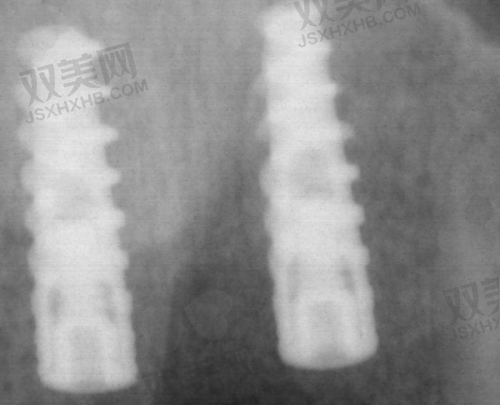

北京瑞鲨口腔医院在技术方面具有诸多特点。首先,医院引进了精良的口腔医疗设备,如口腔 CT、数字化正畸系统、激光治疗设备等。这些设备能够为医生提供更加正确的诊断信息,提高治疗的精细度和成效。例如,口腔 CT 可以清晰地显示牙齿和颌骨的内部结构,帮助医生更好地制定治疗方案。数字化正畸系统则能够实现牙齿矫正的数字化设计和模拟,让患者提前看到矫正后的成效。其次,医院注重技术创新和人才培养,不断引进国内外精良的口腔医疗技术和理念,并定期组织医生参加学术交流和培训活动,提升医生的技术水平和综合素质。此外,医院还采用了个性化的治疗方案,根据患者的不同情况,制定更适合的治疗方案,确保治疗成效达到至佳。